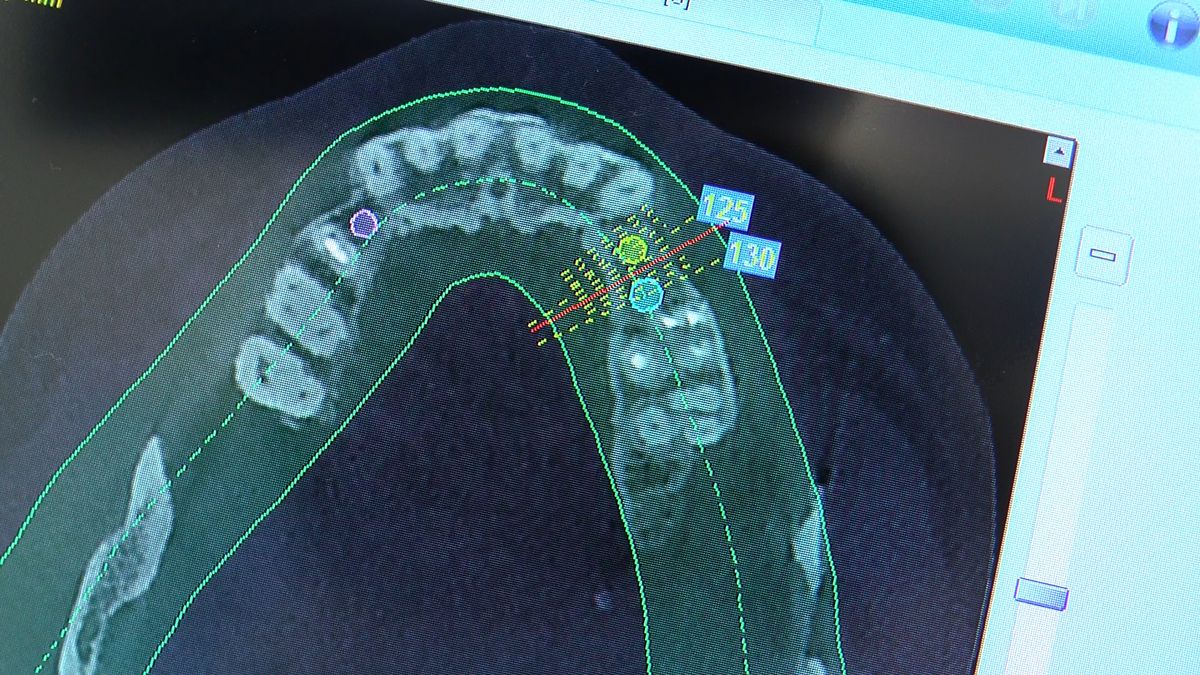

Pierwszy weekend 2019 roku w Instytucie Vivadental, to doskonałe otwarcie kolejnego roku edukacyjnego i szkolenia naszych Kursantów. W drodze do sukcesu w implantologii zdobywają wiedzę i umiejętności, a każdy kolejny zabieg to impuls i inspiracja do twórczego rozwoju w leczeniu własnych Pacjentów. Rozpoczęliśmy od sesji praktycznej implantologicznej właśnie z udziałem Pacjentów, na której dominowały samodzielne zabiegi wykonywane pod kierunkiem Mentorów – dr n.med. Violetty Szycik i dr n.med. Magdaleny Kisłowskiej – Syryczyńskiej. W ciągu dwóch dni zabiegowych przyjęliśmy 14 Pacjentów, przeprowadziliśmy zabiegi chirurgiczne, zabiegi regeneracyjne tkanki kostnej i augmentacji oraz wszczepiliśmy 20 implantów systemu Axiom. W ramach panelu edukacyjnego Sukces Twojego Biznesu odbyły się kolejne zajęcia z NLP, na których nasz Mentor Mariusz Wójcik z Gdańskiej Akademii Umiejętności Menedżerskich, kontynuował wprowadzenie do psychologii i podstaw kierujących decyzjami Pacjentów. Ćwiczenia w wesołej i koleżeńskiej atmosferze były niezwykle pouczające, a jednocześnie stanowiły idealną odskocznię po wyczerpujących zabiegach.